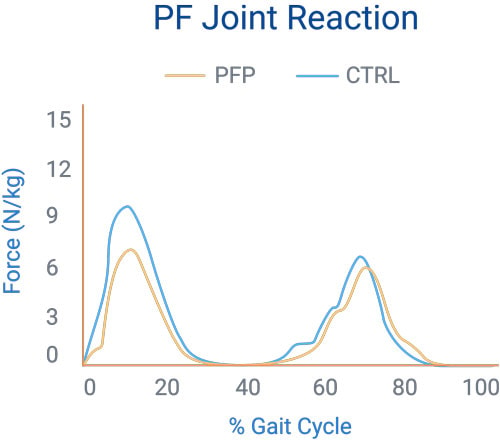

In 2002, Heino et al attempted to show that individuals with PFPS had altered joint loading that resulted in joint stress.They compared the PFJ reaction force, joint stress, and contact area during free and fast walking in subjects with PFPS and asymptomatic controls. On average, those with PFPS had the following characteristics:

Lower joint reaction forcesThese may be attributed to the patients unwillingness to forcefully load their affected limb, according to the researchers.

Higher joint stress and smaller contact areaThese implicate that the improper loading may be causing the anterior knee pain in these patients.